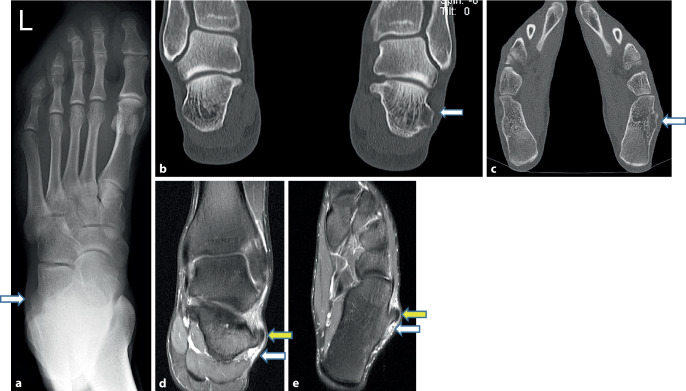

Material and method: A 21-year-old high jump athlete suffered a painful crack on the outer left foot while running a right hand curve without any trauma. Clinically, there was a painful, palpable reproducible dislocation of the peroneus longus tendon probably due to an extremely oversized peroneal tubercle. A local cortisone injection had been given 5 months previously because of local pain. The X‑ray, computed tomography (CT) and magnetic resonance imaging (MRI) examinations showed substantial hypertrophy of the left peroneal tubercle with a riding dislocation of the peroneus longus tendon on it. As conservative therapy was known to be insufficient, surgery was indicated.